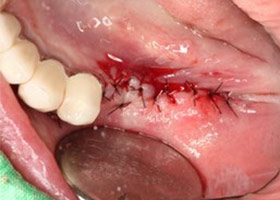

6. 角質化牙齦,再生手術。

![proimages/case/Artificial_implant/save-defeat04-1.jpg proimages/case/Artificial_implant/save-defeat04-1.jpg]()